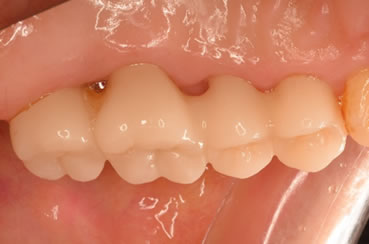

症例3

治療の特徴(患者I様)

初診 2015年5月1日 / 経過 2018年7月2日

| 治療期間 | 2年5カ月(2019年5月時点SPT中) |

|---|---|

| 費用 | 保険内治療 |

| 歯間外科処置 | 1ブロック約9,000円(3割負担) |

| 治療のデメリット | 外科処置を伴う・治療期間が長い(歯槽骨の安定を見る為) 歯周 外科処置後歯肉の位置が下がる為知覚過敏が起こりやすい |